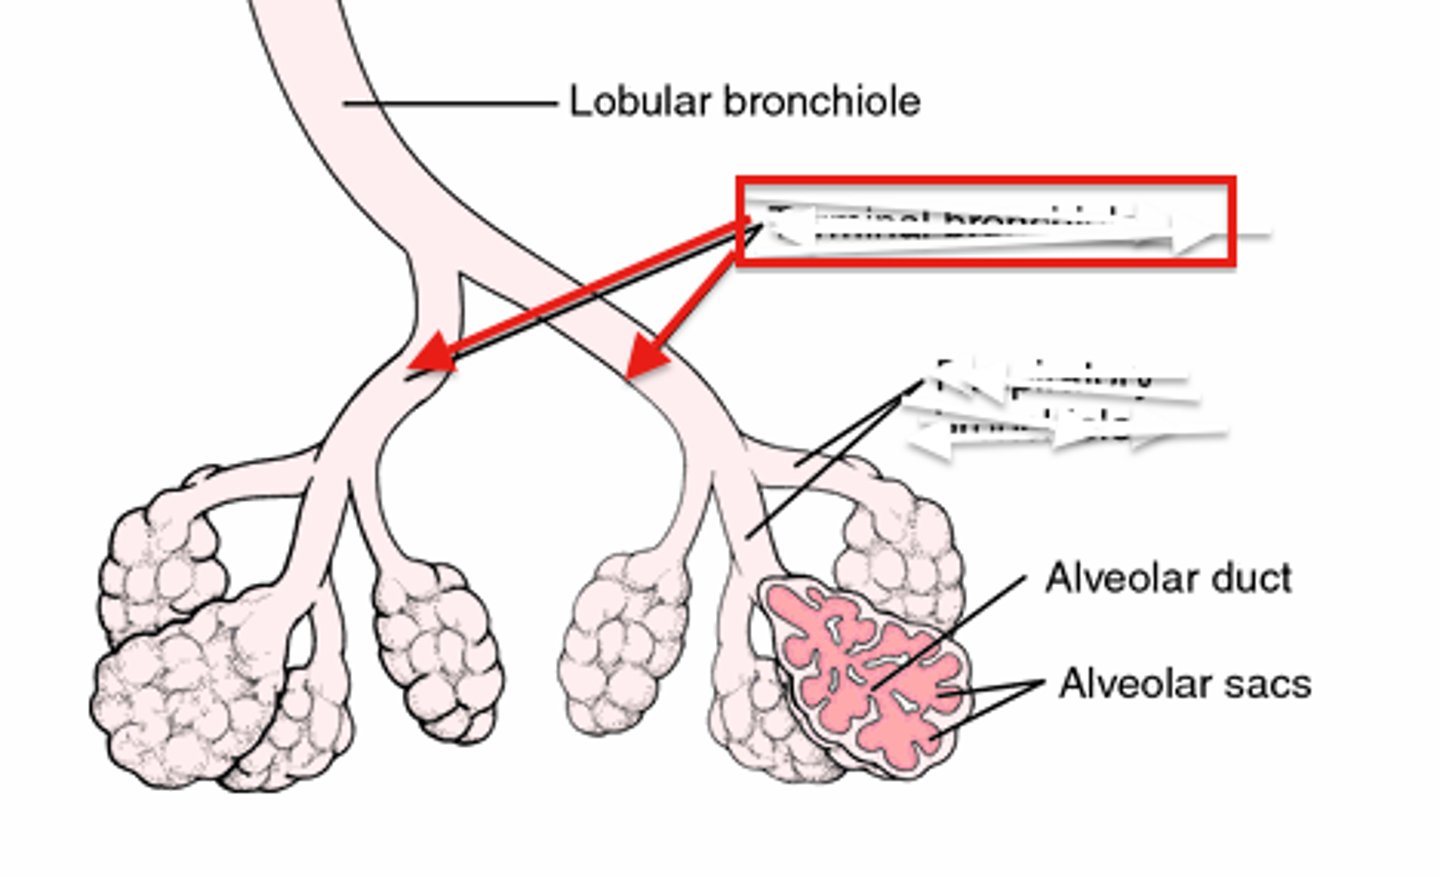

bronchiole

branch of bronchi that are 1 mm or less in diameter and terminate at alveolar sacs

respiratory bronchiole

branches of the terminal bronchioles that subdivide into several alveolar ducts

alveous

small, grape-like sac that performs gas exchange in the lungs

alveoli

tiny sacs of lung tissue specialized for the movement of gases between air and blood

alveolar ducts

Small passages connecting the respiratory bronchioles and the alveolar sacs.

Type I alveolar cells

simple squamous cells where gas exchange occurs

Type II alveolar cells

secrete surfactant